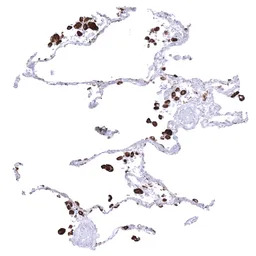

IHC-P analysis of human lung tissue section using GTX04366 Napsin A antibody [MSVA-555R] HistoMAX.

Normal lung showing strong Napsin A immunostaining of pneumocytes and alveolar macrophages.